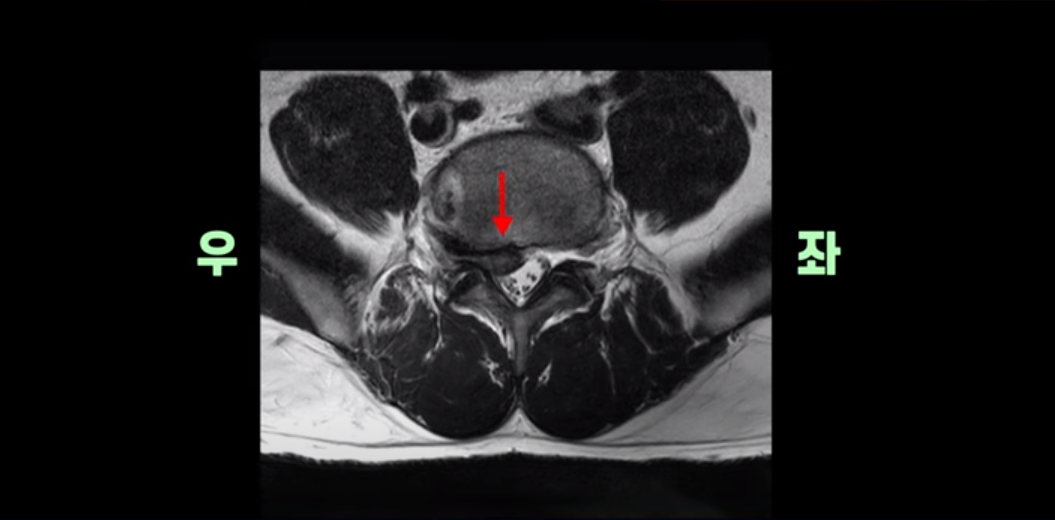

횡단면을 보면 우리 병원 치료 후기에 있는 다른 디스크 파열 환자분들에 비해서는 파열이 덜 심해 보일 수도 있지만,

이분은 파열이 오른쪽으로 치우쳐 신경이 빠져나가는 추간공을 완전히 막고 있습니다.

다른 신경 구멍들은 열려있는데 비해 5번 1번 구멍은 까맣게 막혀있습니다.

이렇게 심하게 신경가지가 눌리니까 극심한 통증은 당연하고 발목에 마비가 생겨 힘이 빠지는 족하수 증상까지 생겼습니다.